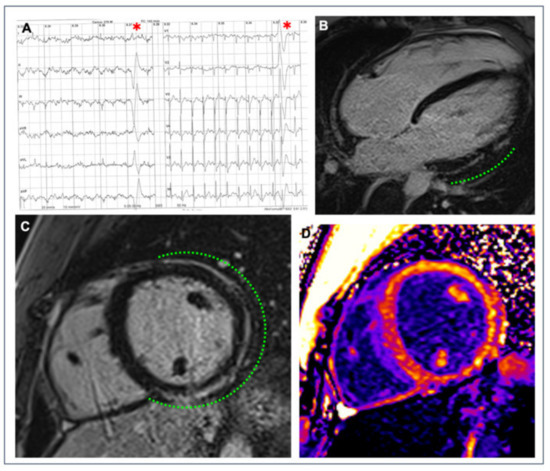

- Zorzi, A.; Marra, M.P.; Rigato, I.; De Lazzari, M.; Susana, A.; Niero, A.; Pilichou, K.; Migliore, F.; Rizzo, S.; Giorgi, B.; et al. Nonischemic left ventricular scar as a substrate of life-threatening ventricular arrhythmias and sudden cardiac death in competitive athletes. Circ. Arrhythmia Electrophysiol. 2016, 9, e004229. [Google Scholar] [CrossRef]

- Marra, M.P.; De Lazzari, M.; Zorzi, A.; Migliore, F.; Zilio, F.; Calore, C.; Vettor, G.; Tona, F.; Tarantini, G.; Cacciavillani, L.; et al. Impact of the presence and amount of myocardial fibrosis by cardiac magnetic resonance on arrhythmic outcome and sudden cardiac death in nonischemic dilated cardiomyopathy. Heart Rhythm 2014, 11, 856–863. [Google Scholar] [CrossRef] [PubMed]